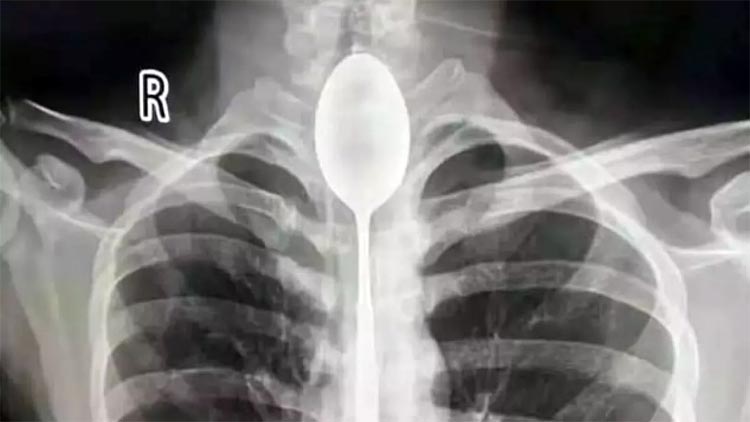

— É preciso ficar atento para o local no qual o alimento está estacionado. A Manobra de Heimlich (pressão sobre o final do diafragma, fazendo com que corpos estranhos sejam expulsos da traqueia) não adianta caso ele já esteja no esôfago, no nível da aorta. Levar imediatamente a pessoa ao hospital é vital, pois somente com um endoscópio o especialista pode verificar em qual local o corpo estranho se alojou e retirá-lo sem comprometer o aparelho digestivo ou qualquer outro órgão.

Em cerca de 90% dos casos, quem chega ao hospital para retirar objetos da via respiratória são crianças. Moedas, bolinhas de gude e peças de brinquedos soltas são as campeãs a serem resgatadas. Não raro, é preciso fazer cirurgias para evitar complicações.

— De uma a duas vezes por mês, pelo menos, entro em bloco cirúrgico para remover corpos estranhos trancados no esôfago, que vão de próteses dentárias mal presas a até Playmobil — afirma o gastroenterologista Sant’Anna.

OBJETOS BIZARROS JÁ ENCONTRADOS

:: Garfo

:: Faca